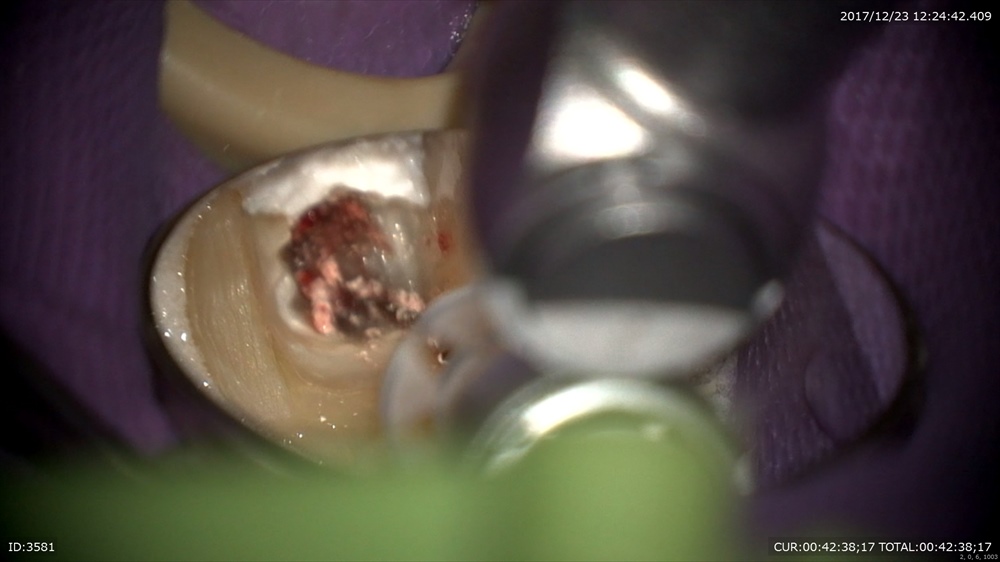

最後の患者さまも精密根管治療で歯の保存。今日は3回目。最後の感染源(汚れ)にアタック!

マイクロエキスカで

そーっと

そして根管充填